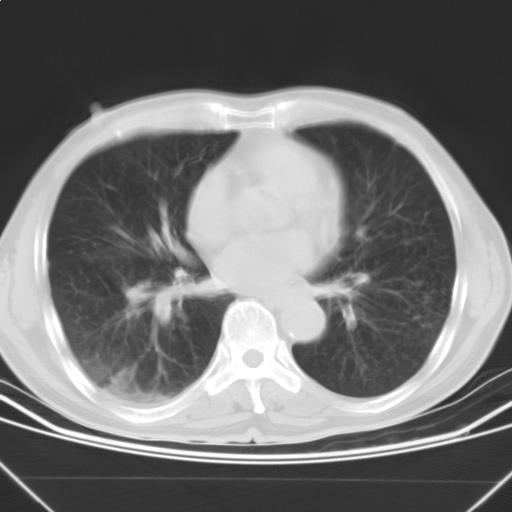

以下是引用随光逐影在2009-5-1 13:53:00的发言:[br]考虑为:1)两肺血行播散型肺结核;2)右肺下叶炎症感染。3)右侧胸膜增厚。